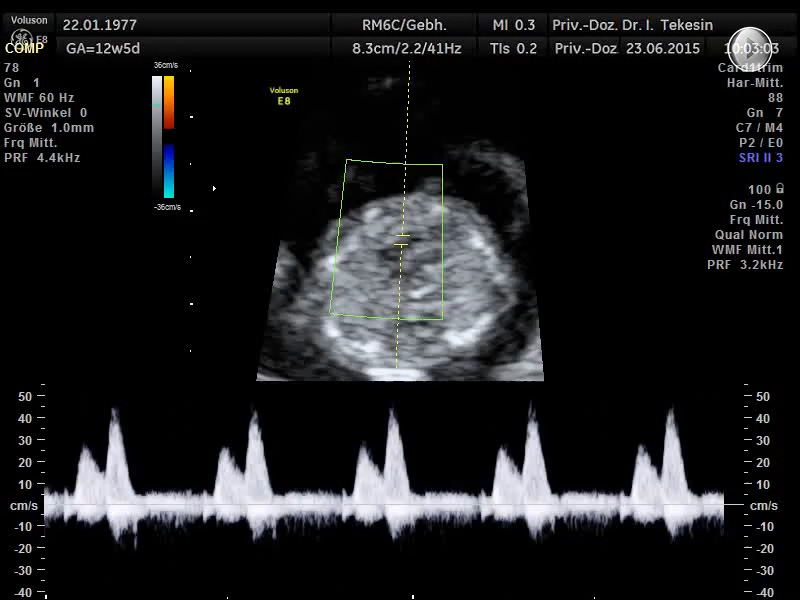

Dopplersonographie

Auch das Durchblutungsverhalten in der Nabelschur und in den Gebärmuttergefäßen wird mit Hilfe des Doppler-Ultraschalls dargestellt. Diese Untersuchung ist eine ergänzende Untersuchung im Rahmen der US-Feindiagnostik und ermöglicht eine Beurteilung des Blutflusses in den kindlichen und mütterlichen Gefäßen mittels einer speziellen Technik. Bei dieser Untersuchung wird die Blutströmung farbig und akustisch dargestellt. Die Geräusche, die man während der Untersuchung hören kann, entstehen durch technische Effekte (Doppler-Effekt), welche der Untersucher und die werdende Eltern hören können, jedoch nicht das ungeborene Kind.

Durch Darstellung der Blutflussmuster in den mütterlichen Gefäßen (Arterie uterina rechts und links) zwischen der 20.-25. SSW können Feten mit dem Risiko einer späteren Mangelversorgung (Plazentainsuffizienz) entdeckt und somit im weiteren Schwangerschaftsverlauf optimal überwacht werden. Ein erhöhtes Risiko für die Entwicklung einer Präeklampsie (mütterlicher Bluthochdruck und Eiweißausscheidung im Urin) kann ebenso festgestellt werden.

Die Beurteilung des Blutflusses in den kindlichen Gefäßen (Nabelschnurarterie [A. umbilicalis], A. cerebri media und Ductus venosus) ermöglicht eine Aussage zur Versorgung des ungeborenen Kindes. Die Doppleruntersuchung kann in unterschiedlichen Zeitpunkten der Schwangerschaft durchgeführt werden.